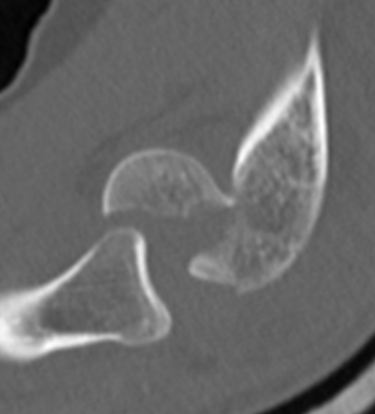

Coronal shear fracture of the distal humerus

Capitellum +/- trochlea

Double arc sign seen on xray

Double arc sign on xray